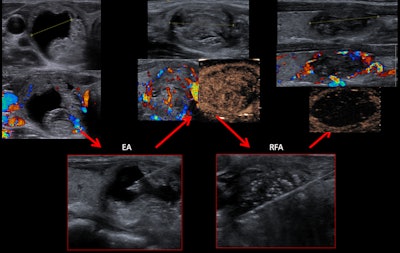

A 38-year-old woman with a solid-cystic nodule was treated with ethanol ablation (EA) before the RF ablation.Also, they observed that the usefulness of ethanol ablation in solid-cystic nodules has reemerged with the introduction of RF ablation.